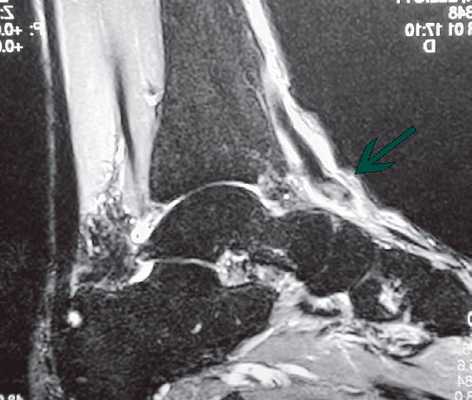

Магнитно-резонансную томографию (МРТ). Этот метод позволяет визуализировать мягкотканные структуры, например, мышцы и сухожилия. МРТ назначается в случаях, когда диагноз вызывает сомнения.

Информативным методом диагностики разрывов сухожилия передней большеберцовой мышцы является магнитно-резонансная томография. В случаях, когда пациент обращается достаточно поздно и уже не помнит факта травмы или провоцирующего события, МРТ может помочь поставить диагноз разрыва или дегенерации сухожилия передней большеберцовой мышцы.

МР-томограммы с признаками разрыва сухожилия передней большеберцовой мышцы слева в области его прикрепления. А, На уровне ладьевидной кости, где сухожилие должно располагаться к тылу от нее, его не видно. В, На сухожилие передней большеберцовой мышцы выглядит волнистым из-за отсутствия натяжения. Сухожилие заканчивается расширенной культей к тылу от ладьевидной кости.

Оптимально точной диагностической методикой определения тех или иных патологий сухожилий, на сегодняшний день, является МРТ. Именно МРТ наилучшим образом способствует выявлению целого спектра повреждений и дегенеративных изменений, имеющихся в стопе, а также позволяет отличить наличие воспалительного процесса от разделения сухожилия.